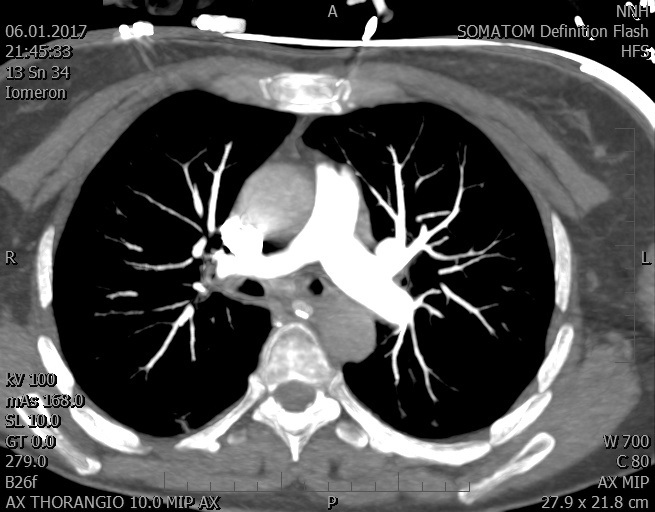

Video 1 - Akutní koronarografie prokázala normální nález na věnčitých tepnách s výjimkou suspekce na lehký spasmus na pravé koronární tepně.Echokardiograficky byla zjištěna těžká dysfunkce dilatované levé komory s nezvětšenou pravou komorou (video 2).

Video 2 - Echokardiograficky byla zjištěna těžká dysfunkce dilatační levé komory s nezvětšenou pravou komorou.Pro nejasnou příčinu zástavy jsme provedli i vyšetření výpočetní tomografií (CT), které vyloučilo plicní embolizaci (série 1 - soubory na konci článku). V den přijetí při přetrvávající oběhové nestabilitě byla nemocná opakovaně defibrilována pro fibrilaci komor se stabilizací rytmu po podání amiodaronu a mesocainu. Dle hemodynamických měření se jednalo o těžký kombinovaný šok. Vstupní laboratorní vyšetření bylo bez větších pozoruhodností. Posléze jsme doplnili anamnézu od příbuzných a zjistili, že pacientka užila do dvou hodin před srdeční zástavou první tabletu amoxicilinu na lehký respirační infekt. Při nevýtěžnosti vstupních vyšetření a nových anamnestických informacích jsme doplnili 14 hodin po kolapsu vyšetření koncentrace tryptázy v séru, která byla extrémně zvýšena (tabulka 2), což nás vedlo k podezření na anafylaxi.